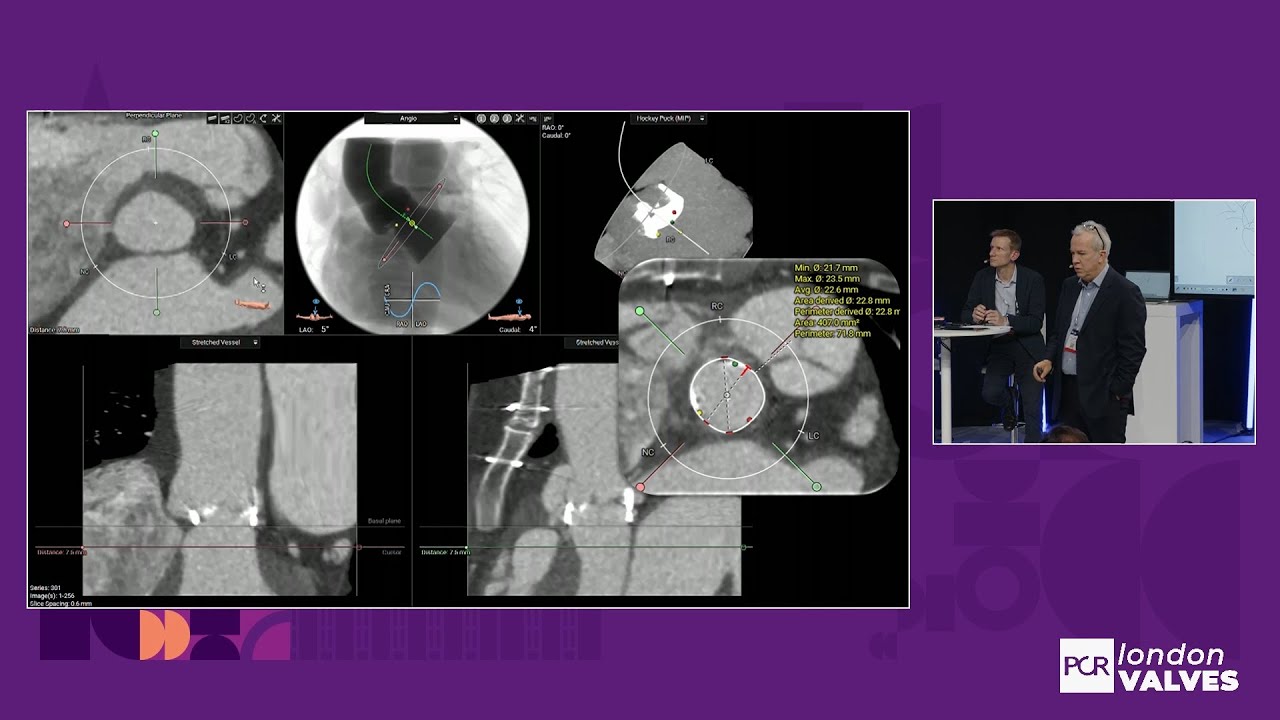

How to handle the most clinically relevant challenges in TAVI

TAVI for bioprosthetic valve failure: LIVE Educational Case from Institut Cardiovasculaire Paris Sud - Massy, France